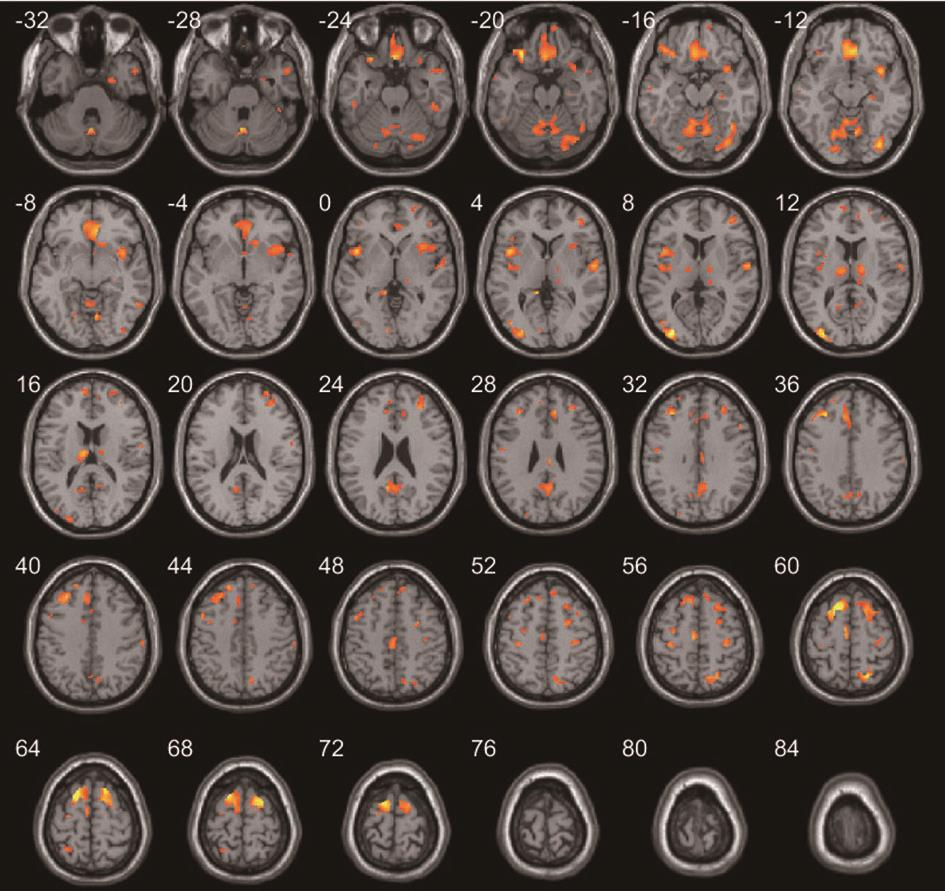

• 正常成人与伴吞咽障碍的急性脑梗死患者吞咽相关脑功能区激活机制的血氧水平依赖功能磁共振研究

摘要:目的 运用血氧水平依赖功能磁共振(blood oxygenation level dependent-functional magnetic resonance imaging,BOLD-fMRI)技术对伴吞咽功能障碍的急性脑梗死患者和正常成人在吞咽活动时相应的脑功能区域激活特点进行研究,探索急性脑梗死患者吞咽功能障碍恢复过程中相关的脑功能区域调控方式。方法 选取2018年7月至2021年7月在昆明医科大学附属延安医院住院的伴吞咽障碍的急性脑梗死患者150例和正常成人100例,对其进行BOLD-fMRI扫描,记录两者在吞咽活动时相关脑功能区域的激活体积和强度,并对比两者间的差异。结果 共收集病例组150例,其中右侧脑梗死组患者50例,男29例,女21例,平均年龄(56.22±7.33)岁;左侧脑梗死组患者100例,男61例,女39例,平均年龄(58.07±6.84)岁;对照组100例,男57例,女43例,平均年龄(53.56±11.41)岁。对照组吞咽活动时激活的相关脑功能区域特点显示:两侧初级运动皮层中枢(BA4区)、运动前区/辅助运动区(BA6/8区)、缘上回(BA40区)、岛叶(BA13区)、颞上回(BA22区)、扣带回皮层(BA24区)、额叶内侧面(BA32区)、延髓、脑桥、基底核团、丘脑、小脑及左侧颞极(BA38区)和右侧颞横回(BA41区)等脑功能区激活体积和强度增加,左侧BA4区、BA40区、小脑激活体积较右侧大,差异有统计学意义(P<0.05);左右两侧脑区的激活强度差异无统计学意义(P>0.05)。右侧脑梗死病例组患者BOLD-fMRI扫描各脑区激活体积显示:右侧BA4区、BA6/8区激活体积较对照组减小,左侧BA6/8区、BA4区激活体积较对照组增大,双侧后扣带回皮层的BA23和顶叶内侧面BA31区体积较对照组增大,左侧视觉中枢的BA18/19和BA41区皮层激活体积较对照组增大,差异有统计学意义。右侧BA4区、BA6/8区、BA40区、BA13区激活强度较对照组降低,差异有统计学意义。左侧脑梗死病例组患者BOLD-fMRI扫描各脑区激活体积显示:左侧BA4区、BA6/8区的激活体积较对照组减小,右侧BA4区、BA6/8区激活体积较对照组增大,双侧BA23/31区、左侧BA41区、双侧BA7区、双侧BA18/19区和双侧小脑激活体积较对照组增大,差异有统计学意义。左侧BA4区、BA6/8区、BA40区、BA13区激活强度较对照组降低,差异有统计学意义。结论 双侧运动、运动前、感觉、嗅觉、听觉、脑干、小脑、基底核团等脑功能区均参与调控正常人的吞咽活动,且调控具有一定的偏侧性。同侧的运动功能区、运动功能前区激活体积降低,对侧运动功能区、运动功能前区激活体积增加是伴吞咽障碍的急性脑梗死患者吞咽相关脑功能区的主要代偿特点。